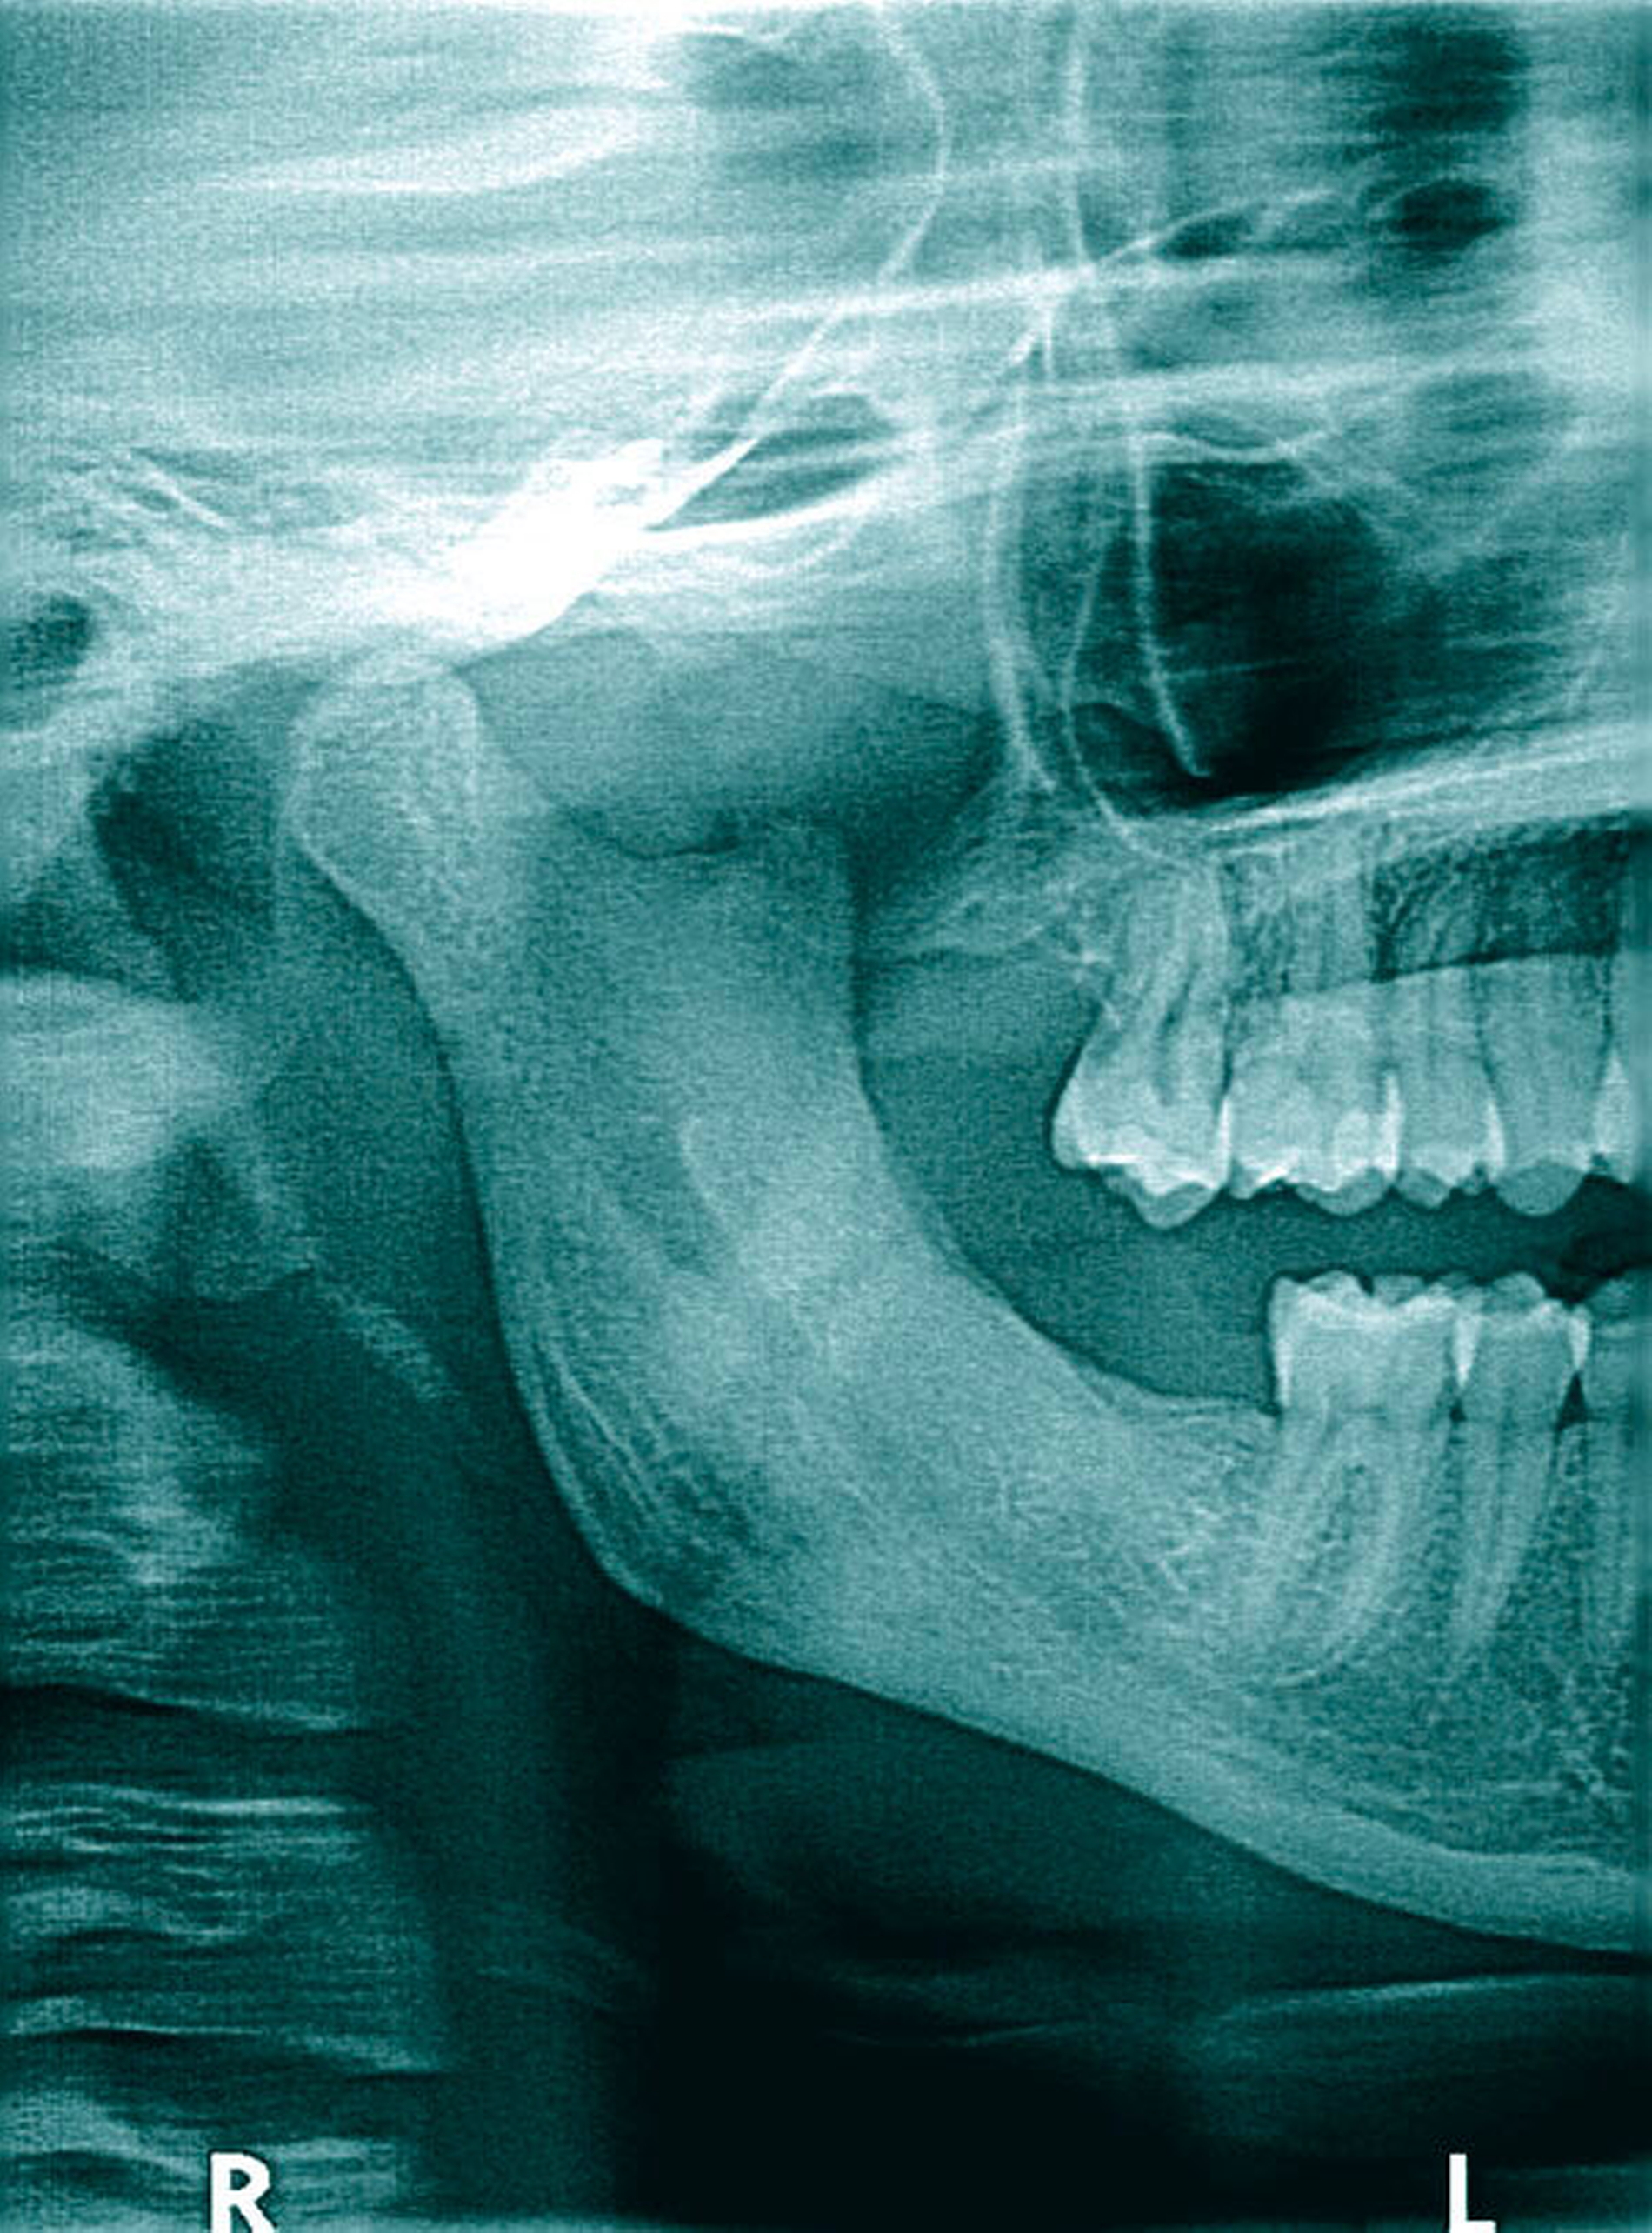

Eine gesunde 23-jährige Patientin stellte sich mit einem submukösen Abszess und beginnendem Wangeninfiltrat rechts bei Zustand nach Weisheitszahnentfernung der Zähne 18, 28, 38, 48 (Abbildung 1) alio loco im Notdienst unserer MKG-chirurgischen Abteilung Anfang 2015 vor. Nach Abszessinzision, Drainage und Gabe eines oralen Antibiotikums (Clindamycin) kam es zunächst schnell zu einer Verbesserung der klinischen Situation, so dass nach unserer Behandlung die weitere Nachsorge durch den niedergelassenen Zahnarzt erfolgte.